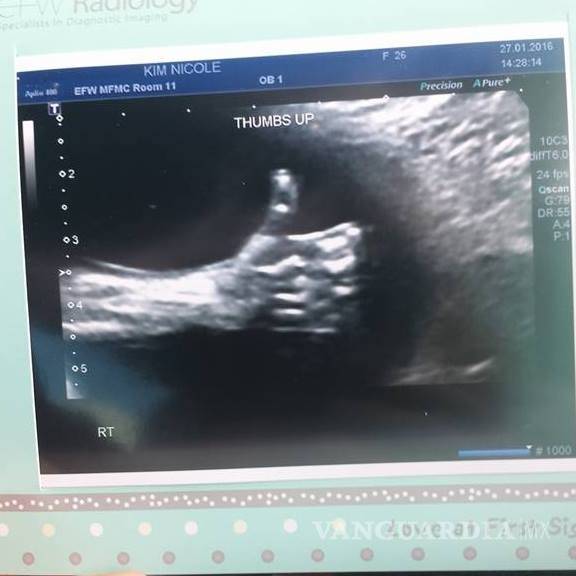

Nicole Kim, la madre, encontró este inspirador mensaje en la ecografía de la semana 20: un pulgar para arriba

Todavía no ha nacido, pero este bebé canadiense tiene un mensaje para sus padres: quiere decirles que todo va a ir bien.

Nicole Kim, la madre, encontró este inspirador mensaje en la ecografía de la semana 20: un pulgar para arriba. Kim contó en la web del programa Today, de la NBC, que el mensaje del bebé llegó justo cuando su padre, Tony, lo acababan de echar del trabajo.

En una entrevista con el Calgary Herald, Kim contó también que el técnico de la clínica de Calgary donde hizo la ecografía le dio rápidamente al zoom y tomó la foto cuando vio al bebé con el pulgar levantado.